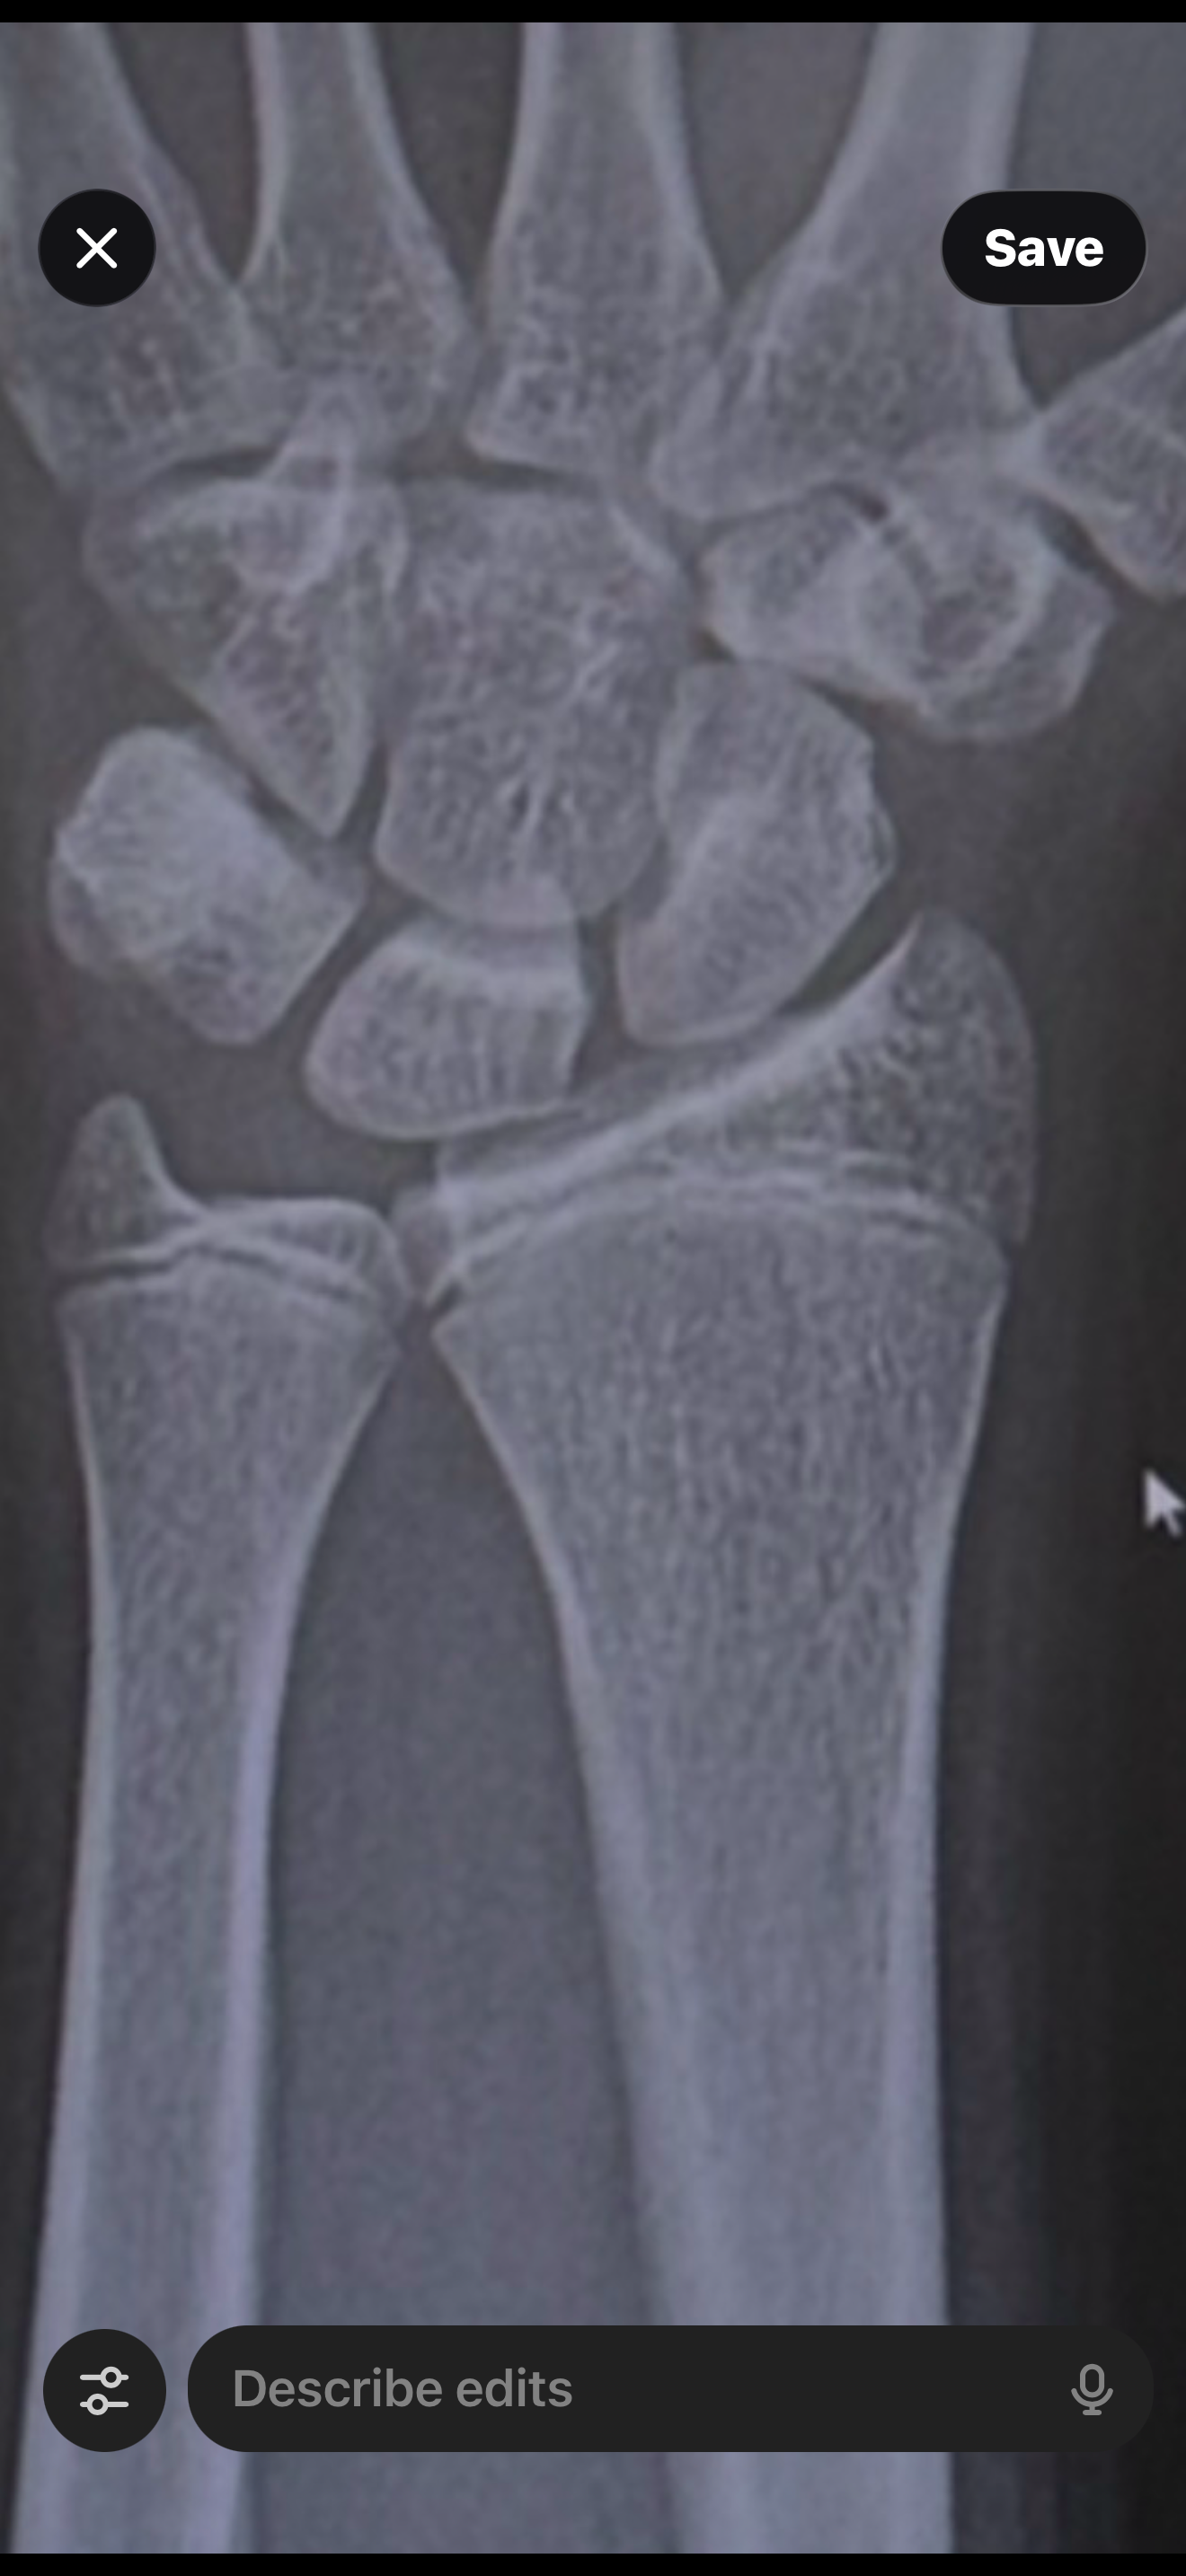

That’s legit 2-2.5 AT LEASTLiterally impossible with that scan of ur wrist, gpt is retarded

U can see my wrist plates open I have about 2 inches and I grow a moustache and slight fizzle on neck and chin

As u know knees close after wrist so

But bro I got a question what u think of my plates

Seems fine to meBut bro I got a question what u think of my plates

Yeah u think I got 2+ inches like 2-3?Seems fine to me

What u think of my plates tho?

That was like 5 months agoView attachment 4830693

I'd estimate like 5-8cm of growing left? I'm not sure, I'm not particularly good at reading x-rays.